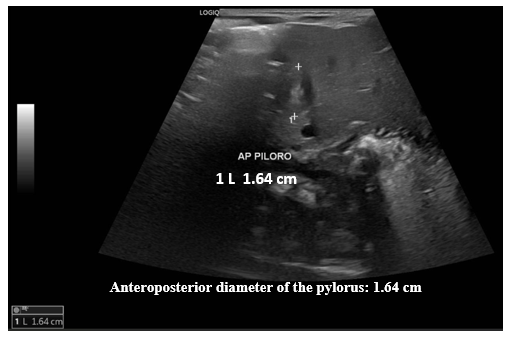

Ultrasound of the abdomen. The liver, gallbladder, bile ducts, pancreas, spleen, right and left kidneys, bladder, and retroperitoneum are normal. Additional examination focusing on the pylorus reveals a pyloric canal diameter of 20 mm, a muscle layer thickness of up to 5 mm, and an anteroposterior diameter of the pyloric canal of 16.4 mm.

Conclusion: Ultrasound findings suggestive of developing pyloric hypertrophy, to be correlated with current clinical presentation (Figures 1–3).

Figure 2 Pylorus ultrasound. Measurement of the anteroposterior diameter (AP) of the pylorus.

Ultrasound images of the pylorus identified an anteroposterior diameter of 1.64 cm.

Ultrasound is the test of choice for the diagnosis of HPS. There are ultrasound parameters that allow the diagnosis of this entity to be made. Among these are the length of the pylorus, the muscle thickness and the diameter of the pylorus. However, there are variations in the measurements of these parameters. Piotto et al.,5 report studies where the measurements of these parameters vary, with pylorus length between 14-20 mm, muscle thickness between 2.5-4.8 mm, and pylorus diameter between 10-25 mm. In their study, Piotto et al.,5 found among 321 neonates without HPS an average length of 2.8 mm, standard deviation (SD) 0.6 mm; muscle thickness of 1.3 mm, SD 0.3 mm; and pylorus diameter of 8.2 mm, SD 1.1 mm. Among 286 neonates with HPS, the mean length was 16.3 mm, SD 2.3 mm, muscle thickness 2.9 mm, SD 0.5 mm, and pyloric diameter 38.4 mm, SD 18.5 mm. The ultrasound findings of our patient identified a diameter of the pyloric canal of 20 mm, a thickness of the muscle layer of up to 5 mm, and an anteroposterior diameter of the pyloric canal of 16.4 mm, all above normal values.